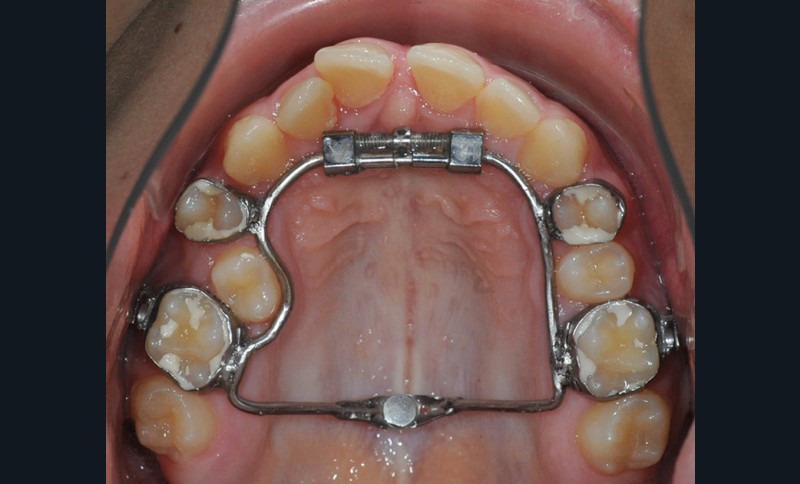

Le début et milieu d’après-midi seront consacrés à l’empreinte numérique, désormais utilisée pour les empreintes d’étude, les set-up, le thermoformage. Les Drs Guillaume Lecocq et Stéphane Desplanques monteront le thermoformage et comment ces empreintes numériques peuvent permettre de confectionner des appareils vestibulaires, linguaux, voire des aligneurs (fig. 1 et 2).